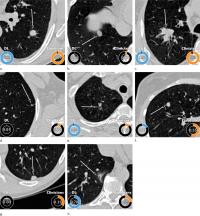

image: Schematic representation of convolutional neural networks (CNNs) used in the deep learning algorithm for malignancy risk estimation of pulmonary nodules detected at low-dose screening CT. Given a CT image and the coordinate of the pulmonary nodule, a three-dimensional (3D) patch that was 50 mm in size and resampled to 64 pixels (px) in each direction was extracted around the nodule. For the two-dimensional (2D) CNN, nine different views were sectioned from the three-dimensional patch. Features were extracted with a ResNet50 CNN for each two-dimensional view, and the features were combined in a fully connected layer. For the three-dimensional CNN, the entire three-dimensional patch was fed as input to an Inceptionv1 three-dimensional CNN. Both architectures had a final layer that produced a continuous output. Finally, the outputs from the two-dimensional and three-dimensional CNNs were averaged in an ensemble to compute the pulmonary nodule malignancy risk between 0 and 1. view more